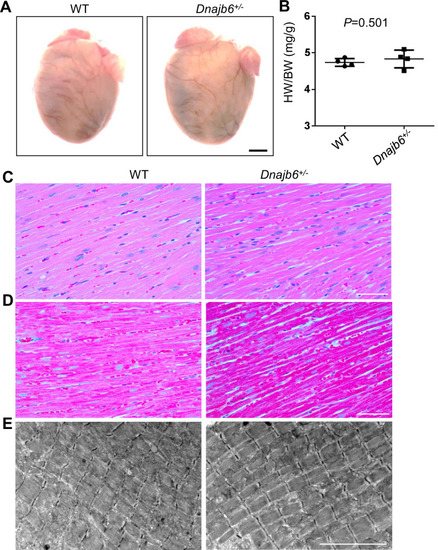

No abnormal myocardium structural remodeling was detected In the Dnajb6+/- mice. (A) Heart morphology of Dnajb6+/- mice compared to WT control at 1 year of age. (B) Quantification analysis of heart weight normalized by body weight (HW/BW) of Dnajb6+/- mice compared to WT control at 1 year of age. N=4, unpaired student t test. (C–E) Shown are histology images of H&E staining (C), Masson’s Trichrome staining (D), and transmission electron microscope (E) indicating the myocardium structure of Dnajb6+/- mice appeared to be indistinguishable to that in WT control. Scale bars in A, 1 mm; In C, D, 100 µm; In E, 5 um. |